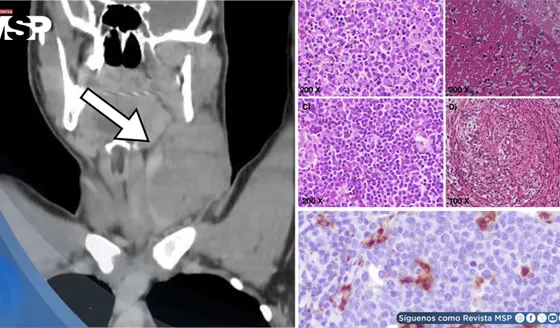

Masa cervical en varón de 17 años es causada por linfadenitis histiocítica necrotizante tipo Kikuchi-Fuji